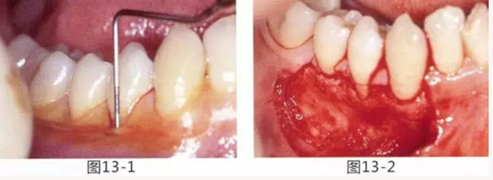

圖13-1 使用碘溶液進行染色,頰側(cè)基本看不到角化牙齦,且無口腔前庭的狀態(tài)。

圖13-2 為了擴張口腔前庭,獲取附著齦而進行了游離齦移植術。受皮床一定不能發(fā)生移動,盡可能使厚度均等。

圖13-3 手術剛結(jié)束的狀態(tài)。通過骨膜縫合的褥式縫合將移植片固定,使其無法移動。

圖13-4 手術完成2年后的狀態(tài)。口腔前庭得到擴張,即使正在進行正畸治療,也沒有妨礙到清潔。